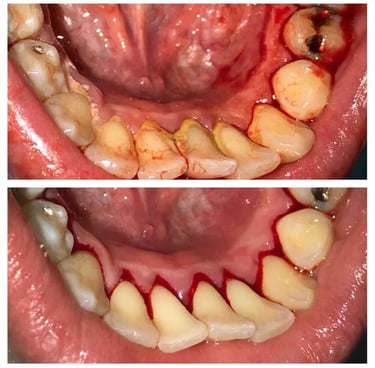

Treatment Results

Deep Cleaning

Deep cleaning, also known as scaling and root planing, is used to treat gum disease by removing plaque and bacteria from below the gum line and smoothing the tooth roots to help gums heal properly. Depending on the severity of the condition, the treatment may be completed in sections (such as half-mouth or quadrant visits) to ensure comfort and thorough care. After deep cleaning, ongoing periodontal maintenance visits every 3–4 months are essential to keep gum disease under control, as regular cleanings are not sufficient once periodontal issues are present.